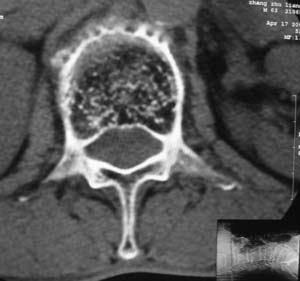

以下是引用余辉在2008-4-27 17:12:00的发言:[br]骨质疏松伴病理性压缩性骨折,椎骨骨松质密度减低,椎体骨小梁稀疏且普遍呈火柴头样改变,椎体无膨胀,无软组织肿块

以下是引用mzh123在2008-4-27 19:33:00的发言:[br]除压缩骨折表现外 还有许莫氏结节改变

以下是引用随光逐影在2008-4-27 21:29:00的发言:[br]除压缩性骨折外,还有许莫氏结节及骨质疏松表现。